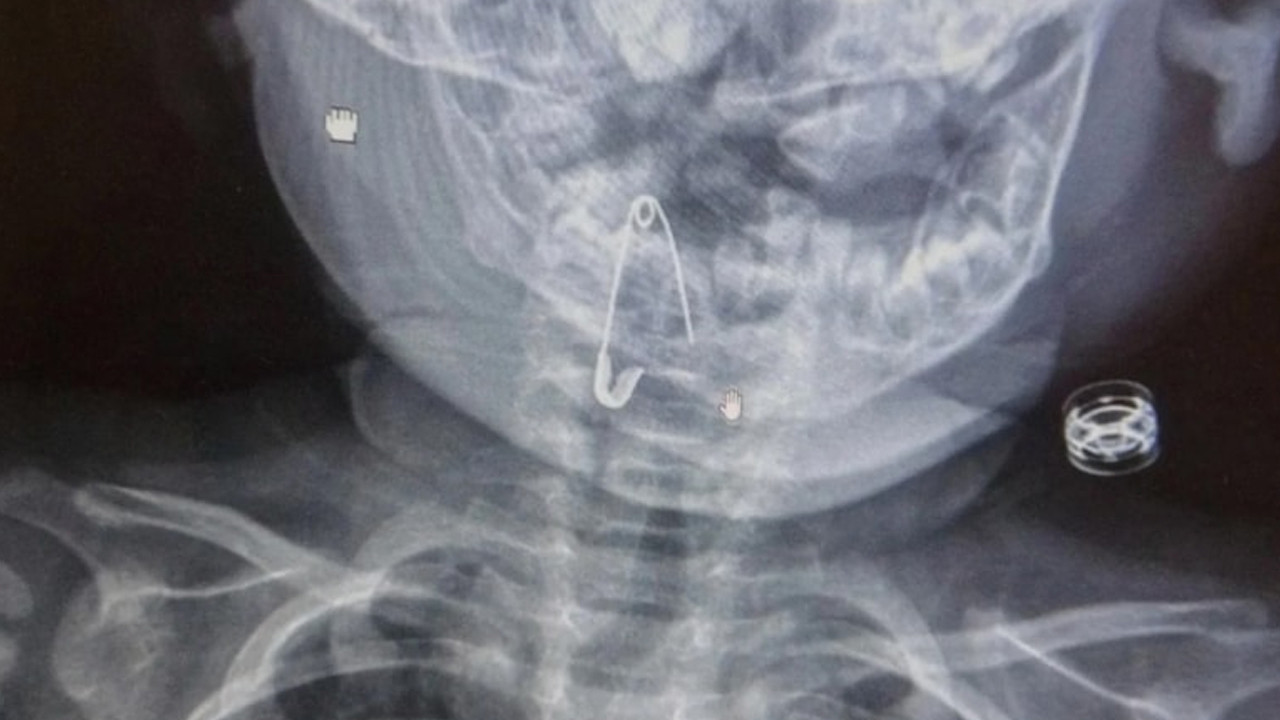

8 aylık bebek çengelli iğne yuttu

Bitlis'in Güroymak ilçesinde 8 aylık bebeğin yuttuğu çengelli iğne, Bitlis-Tatvan Devlet Hastanesinde çıkarıldı.

Abone OlGüroymak ilçesinde çengelli iğne yutan 8 aylık bebek, ailesi tarafından Güroymak Devlet Hastanesine götürüldü. Yapılan kontrollerde çengelli iğnenin soluk borusuna saplandığı tespit edilen bebek, Bitlis-Tatvan Devlet Hastanesine sevk edildi. Burada yapılan müdahaleyle soluk borusundaki çengelli iğne çıkarılan bebek, bir süre gözlem altında tutulduktan sonra taburcu edildi.

Bebeğe müdahale eden Kulak Burun Boğaz Hastalıkları Uzmanı Opr. Dr. Hakan Tuhan, çengelli iğnenin ucunun açık olması nedeniyle bebeğin soluk borusuna saplandığını söyledi.

İğneyi başarılı şekilde çıkardıklarını anlatan Tuhan, "Bebeği 2 saat gözlem altında tuttuktan sonra taburcu ettik. Kulakta, boğazda ve burunda yabancı cisimlerle çok sık karşılaşmaktayız. Çocuklar boncuk, madeni para, nohut, fasulye, mısır gibi şeyleri yutabiliyor ya da kulaklarına, burunlarına sokabiliyorlar. Bu gibi durumlar hayati tehlikeye neden olabiliyor. Ailelerin çok dikkatli olmaları gerekiyor. Bu durumlarla karşılaşan aileler, zaman kaybetmeden en yakın sağlık kuruluşlarına başvurmalı." diye konuştu.